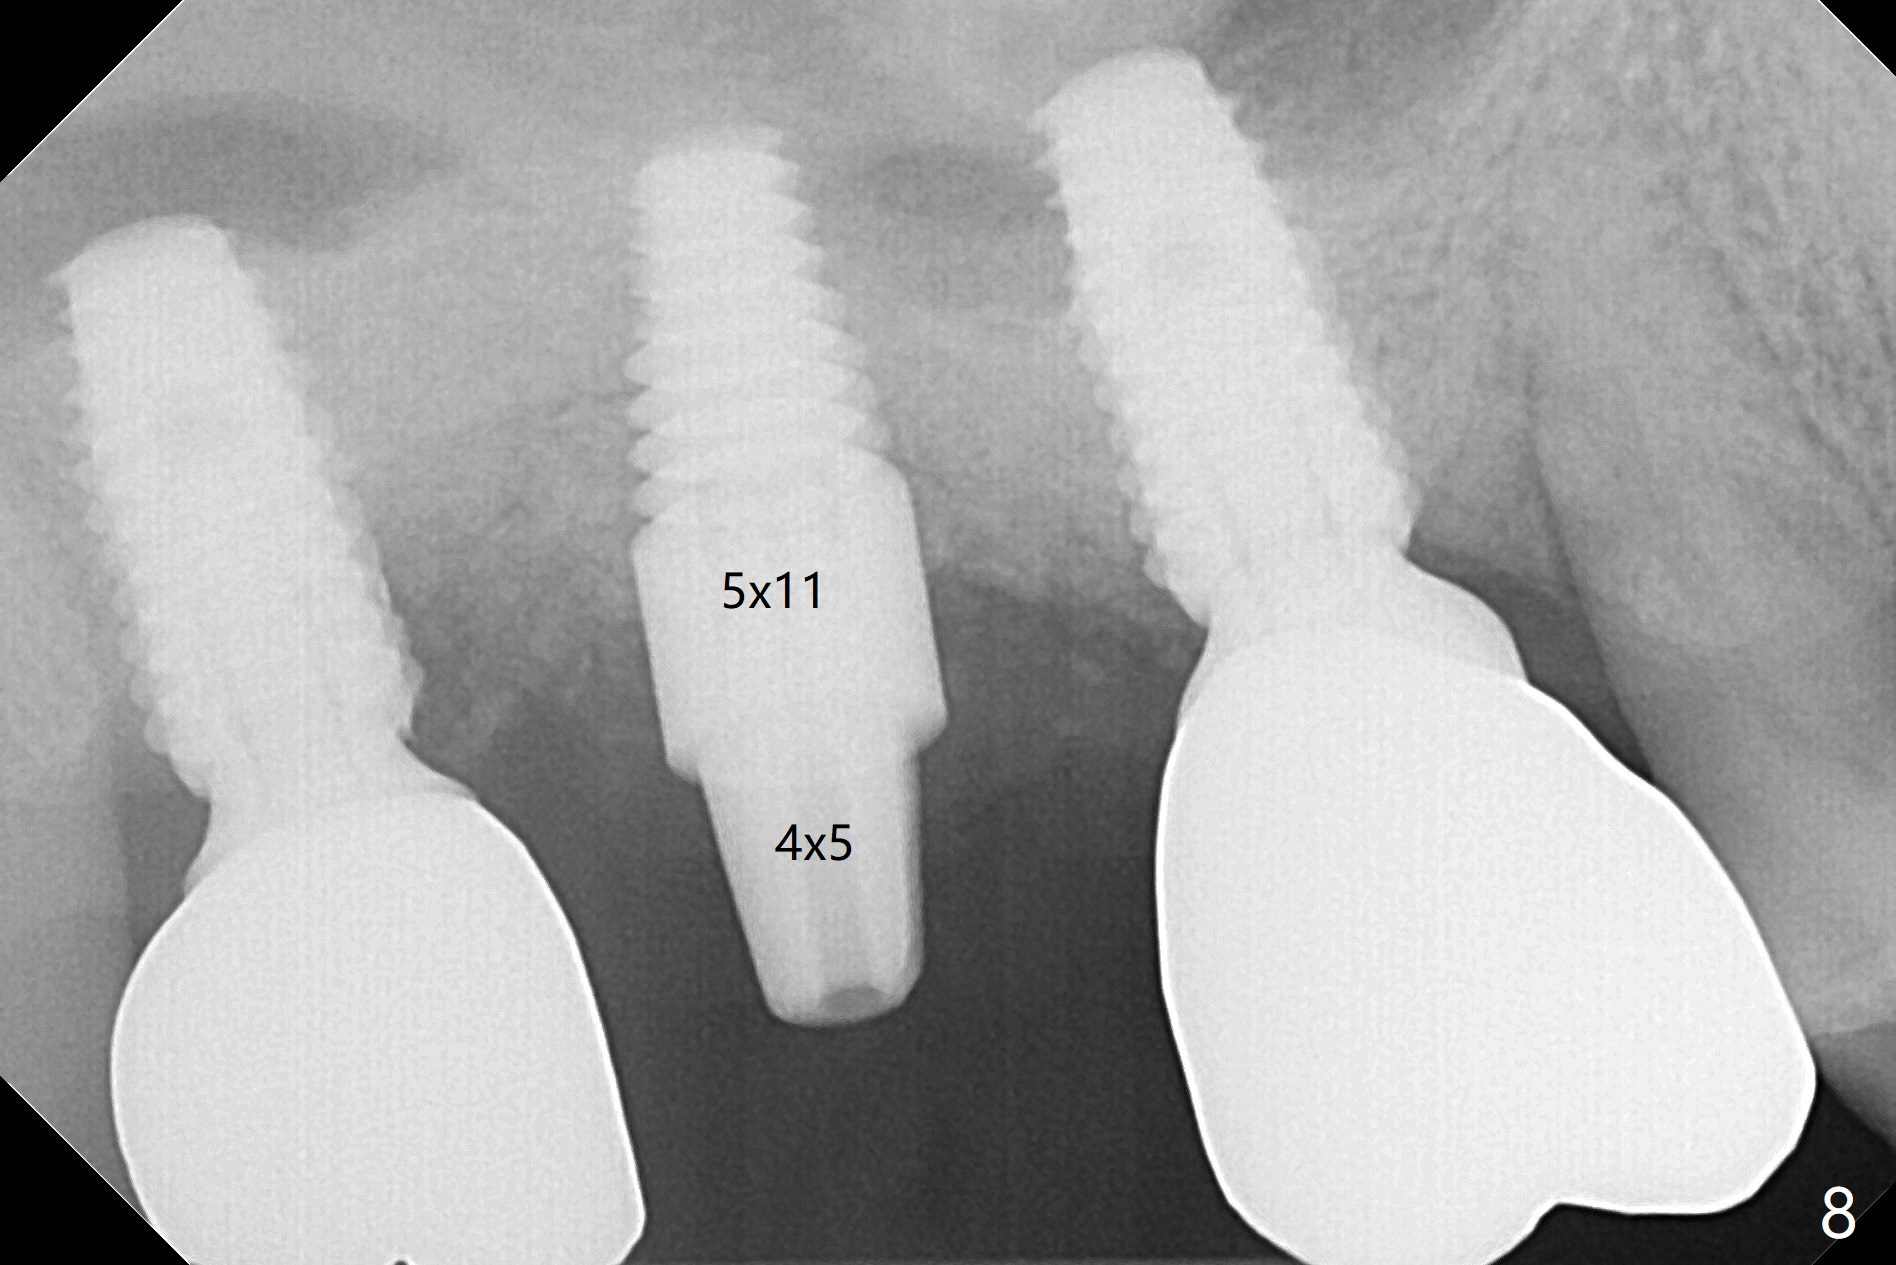

Due to time constraint (he may move out of state), implant placement will be free hand with palatal incision (Fig.5 P).  Surgical stent will be ready.  Since the patient is a heavy bruxer, a 5 or 6 x14 mm tissue-level implant will be placed using DIO Sinus Lift Master Kit and Bone Expander Kit (Fig.6).  Prepare water pump syringe.  The first 6 mm osteotomy with regular drills (1.2 and 2.0 mm) is easy and soft, whereas the last 1-2 mm is hard.  In the end, the sinus membrane is perforated.  After use of 3.5 mm reamer for 8 mm, a 5x14 mm tap is inserted for ~ 8 mm (Fig.7).  A 5x11 mm implant (9 mm in bone) is placed ~ 35 Ncm; following placement of bone graft around the junction of thread and the unpolished portions of the implant, a 4x5 mm abutment is placed for retention of periodontal dressing (Fig.8).  Since #2 implant removal, #3 implant crown/abutment has rotated twice (screw not loose).  On the 2nd occasion (2 months post #2 implant placement), a provisional is fabricated to stabilize #3 crown.  During #2 temporization, the crown of #1 dislodges and recements.  Return to Upper Molar Immediate Implant, Trajectory Similar Case Xin Wei, DDS, PhD, MS 1st edition 01/08/2019, last revision 08/18/2019